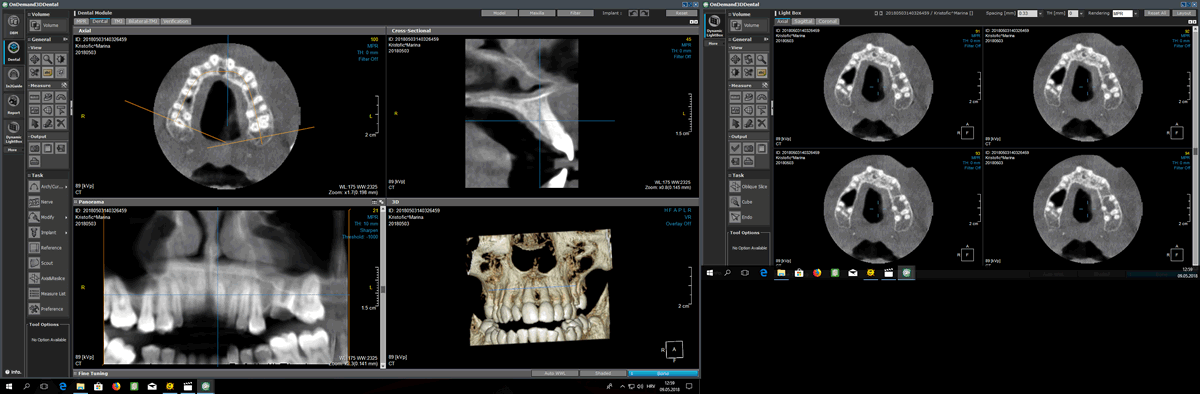

CBCT - je trodimenzionalna snimka zubi i okolne kosti koja se koristi za najdetaljniju i najprecizniju dijagnostiku. Prednost ove snimke je u tome što vidimo zube i okolnu kost u svim dimenzijama. Najčešće nam koristi prilikom implantoloških i kirurških zahvata i kod fraktura zuba.

Snimke se pregledavaju u OnDemand 3D programu.

Uređaj koji mi koristimo ima mogućnosti snimanja u 4 rezolucije. Tako se količina zračenja može kontrolirati i smanjiti ovisno o indikaciji koju postavi Vaš doktor.